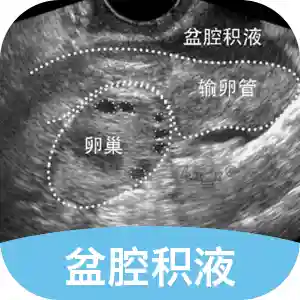

盆腔积液

盆腔炎、附件炎或子宫内膜异位症都可能引起盆腔积液,按病理因素可分为「生理性盆腔积液」和「病理性盆腔积液」。通常情况下,很多女性在常规检查的B超结果上都会提示盆腔积液,但不是每个人都需要治疗,也不影响怀孕,即使做试管婴儿的情况下,盆腔积液也不会影响促排、取卵或胚胎移植,你的盆腔积液你了解吗?关于 盆腔积液 精华问答索引:盆腔积液是什么?盆腔积液就意味着有盆腔炎吗?